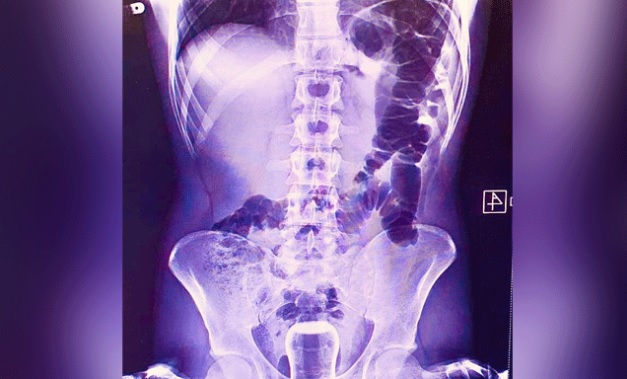

Geçen cuma günü ismi açıklanmayan bir kişi Mehmet Akif İnan Eğitim ve Araştırma Hastanesin’e başvurdu. Acil serviste hastanın çekilen röntgeninde anüs bölgesinde çay bardağı görüldü. Bu kişi genel cerrahi servisinde ameliyata alındı. Çay bardağı, uzman doktorlar tarafından gerçekleştirilen operasyonla çıkarıldı. Ameliyatla sancıdan kurtulup eski sağlığına kavuşan hasta doktorlara, uzun zamandır basur hastası olduğunu, hacamatçıya gittiğini ve yağlı çay bardağın kazayla anüs bölgesine kaçtığını ileri sürerek, ameliyattan dolayı teşekkür etti.